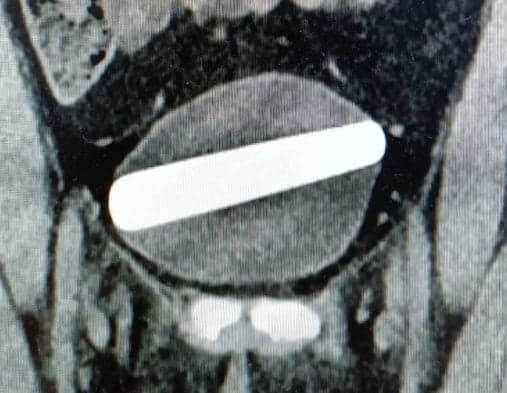

Um fato inusitado aconteceu com uma mulher de 29 anos. Ela precisou passar por uma por um cirurgia para tirar um vibrador de cristal de 10 centímetros e 2,5 de largura inserido acidentalmente no orifício errado.

Sem expor a situação aos profissionais, a paciente precisou passar por um exame de imagem que mostraram o objeto posicionando a bexiga.